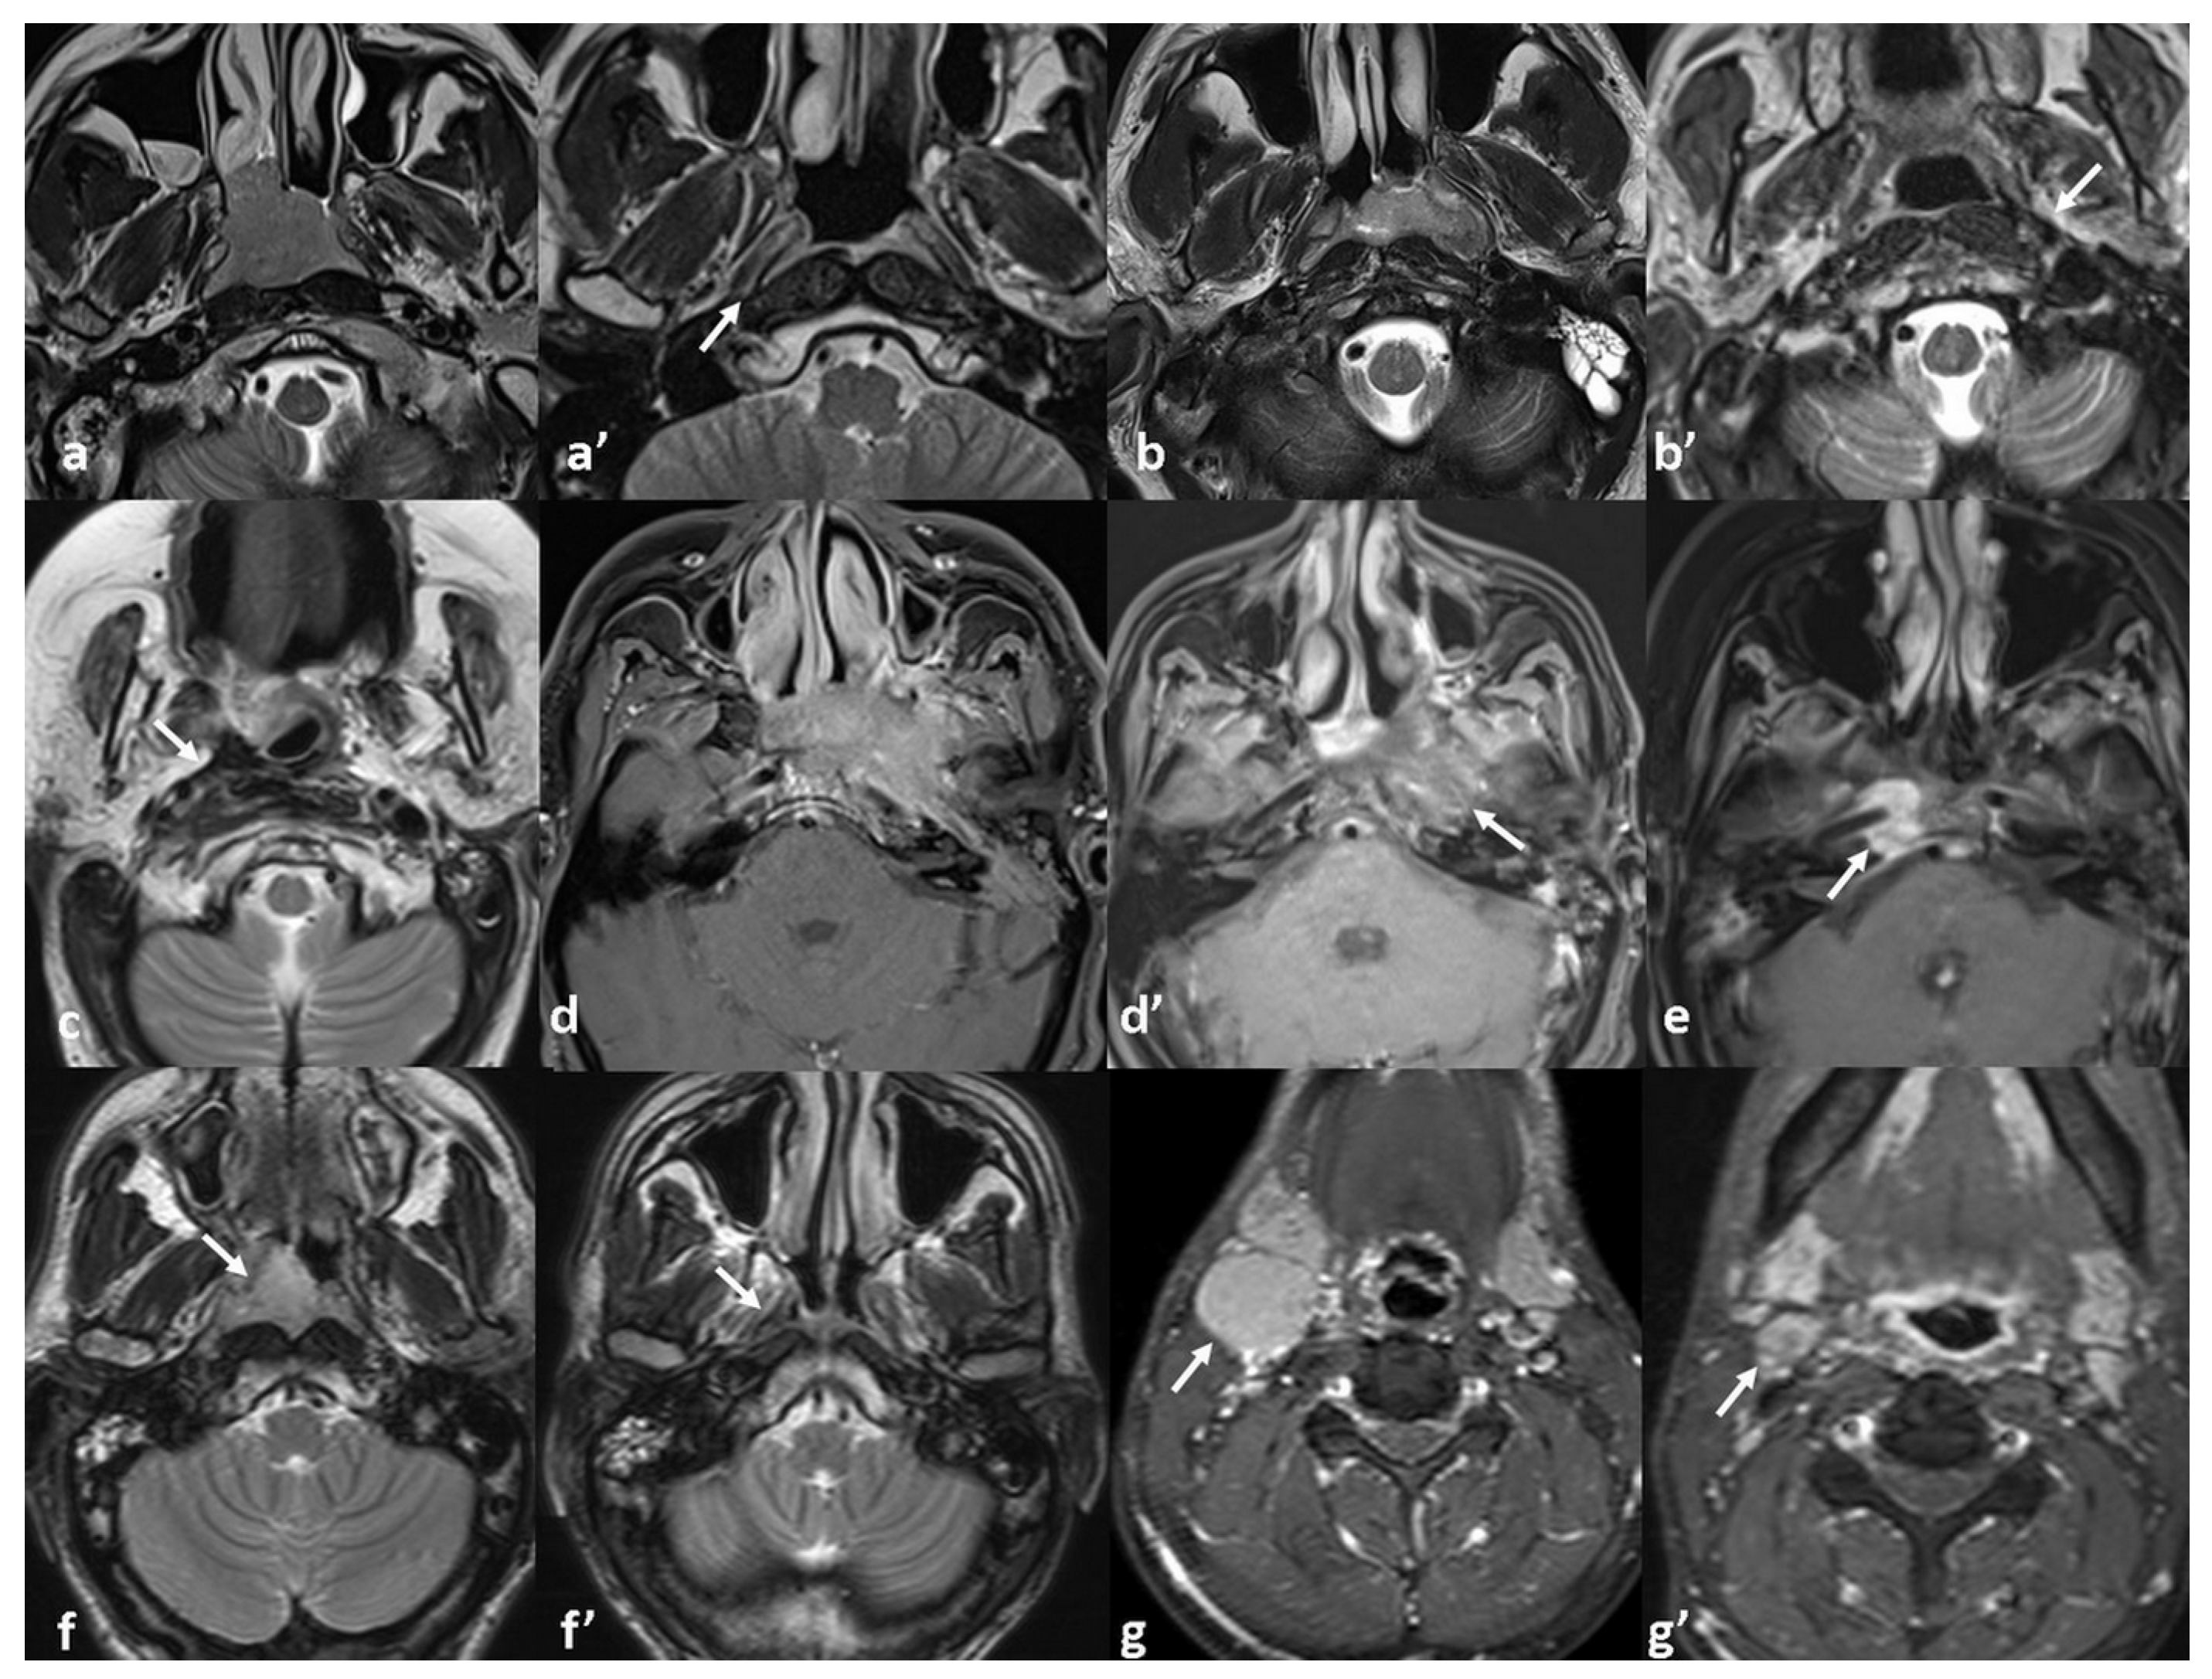

| PPS invasion | 0.001 * | 0.027 * OR: 1.23 95%CI [1.03–1.49] | |

| No | 1/9 (11.1%) | ||

| Local | 3/27 (11.1%) | ||

| Extensive | 10/16 (62.5%) | ||

| SB invasion | 0.521 | ||

| No | 7/32 (21.8%) | ||

| Local | 5/13 (38.4%) | ||

| Extensive | 2/7 (28.5%) | ||

| ICS invasion | 0.008 * | 0.076 | |

| No | 7/41 (17%) | ||

| Local | 5/8 (62.5%) | ||

| Extensive | 2/3 (66.6%) | ||

| Perineural invasion | <0.001 * | 0.029 * OR: 1.60 95%CI [1.05–2.43] | |

| Positive | 7/43 (16.2%) | ||

| Negative | 7/9 (77.7%) | ||